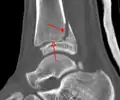

A triplane fracture of the ankle as seen on plain X-ray

A triplane fracture of the ankle as seen on CT

- Triplane fractures are a special type of fracture that involves the immature skeleton. It has a coronal plane in the metaphysis, an axial plane in the physis, and a sagittal plane in the epiphysis.[14]